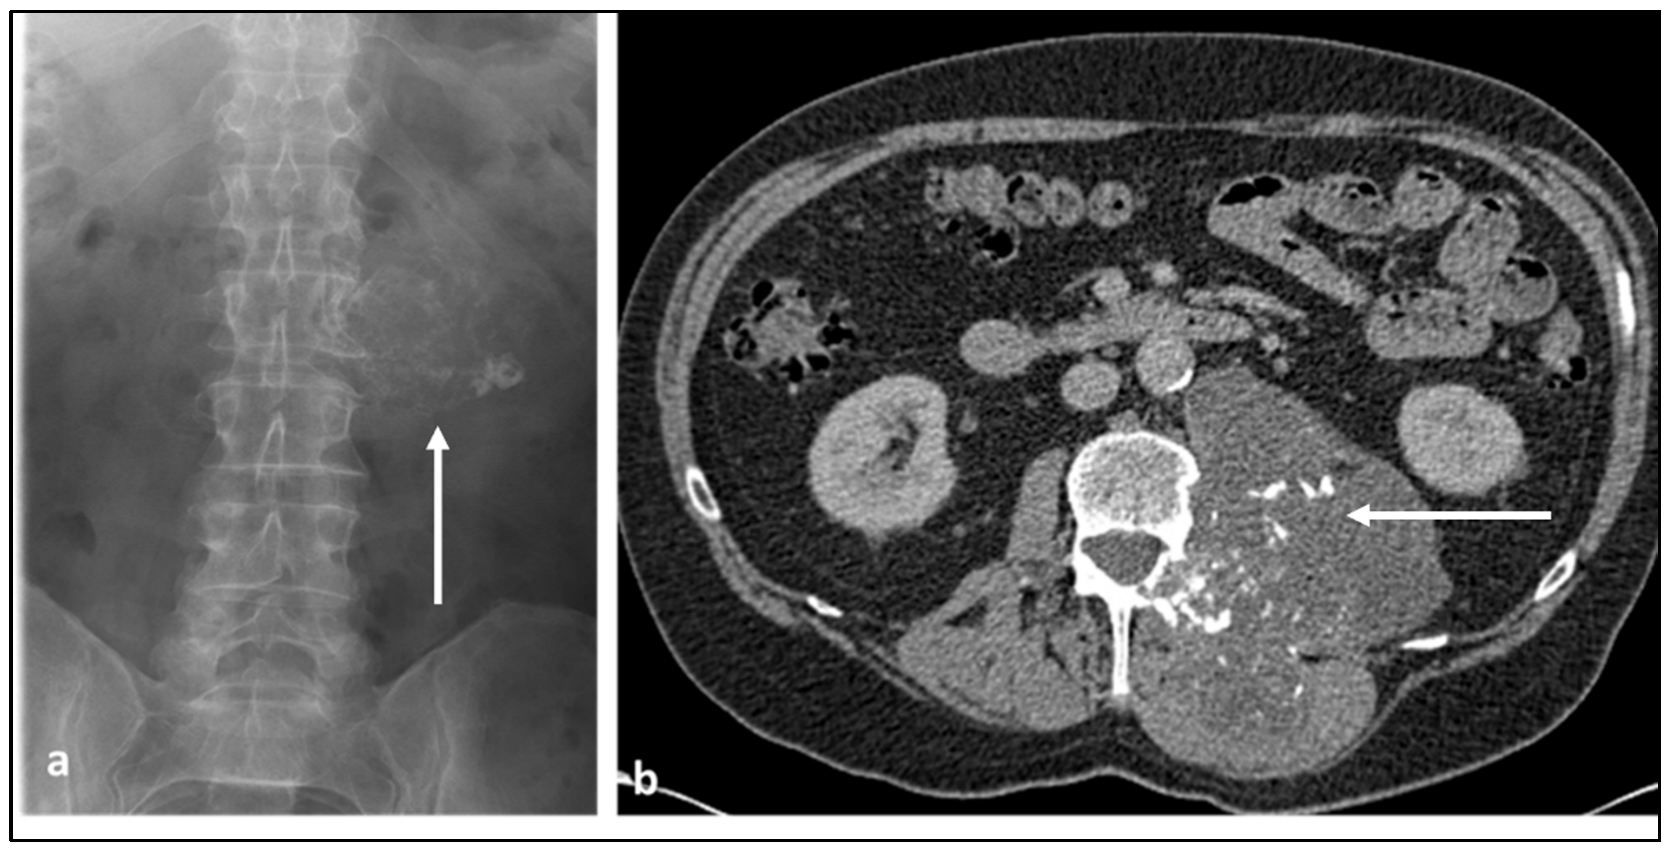

3.3. Chondrosarcoma

| Chondrosarcoma | Lytic lesion. ‘Rings and arcs’ calcification characteristic of chondroid matrix. | High T2 signal due to cartilage and myxoid content. Peripheral and septal enhancement. Enhancing extra-osseous soft tissue component. |